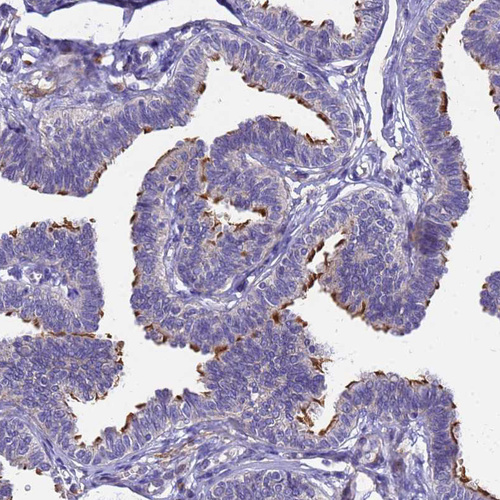

Immunohistochemical staining of human cerebral cortex shows moderate cytoplasmic positivity in neurons.